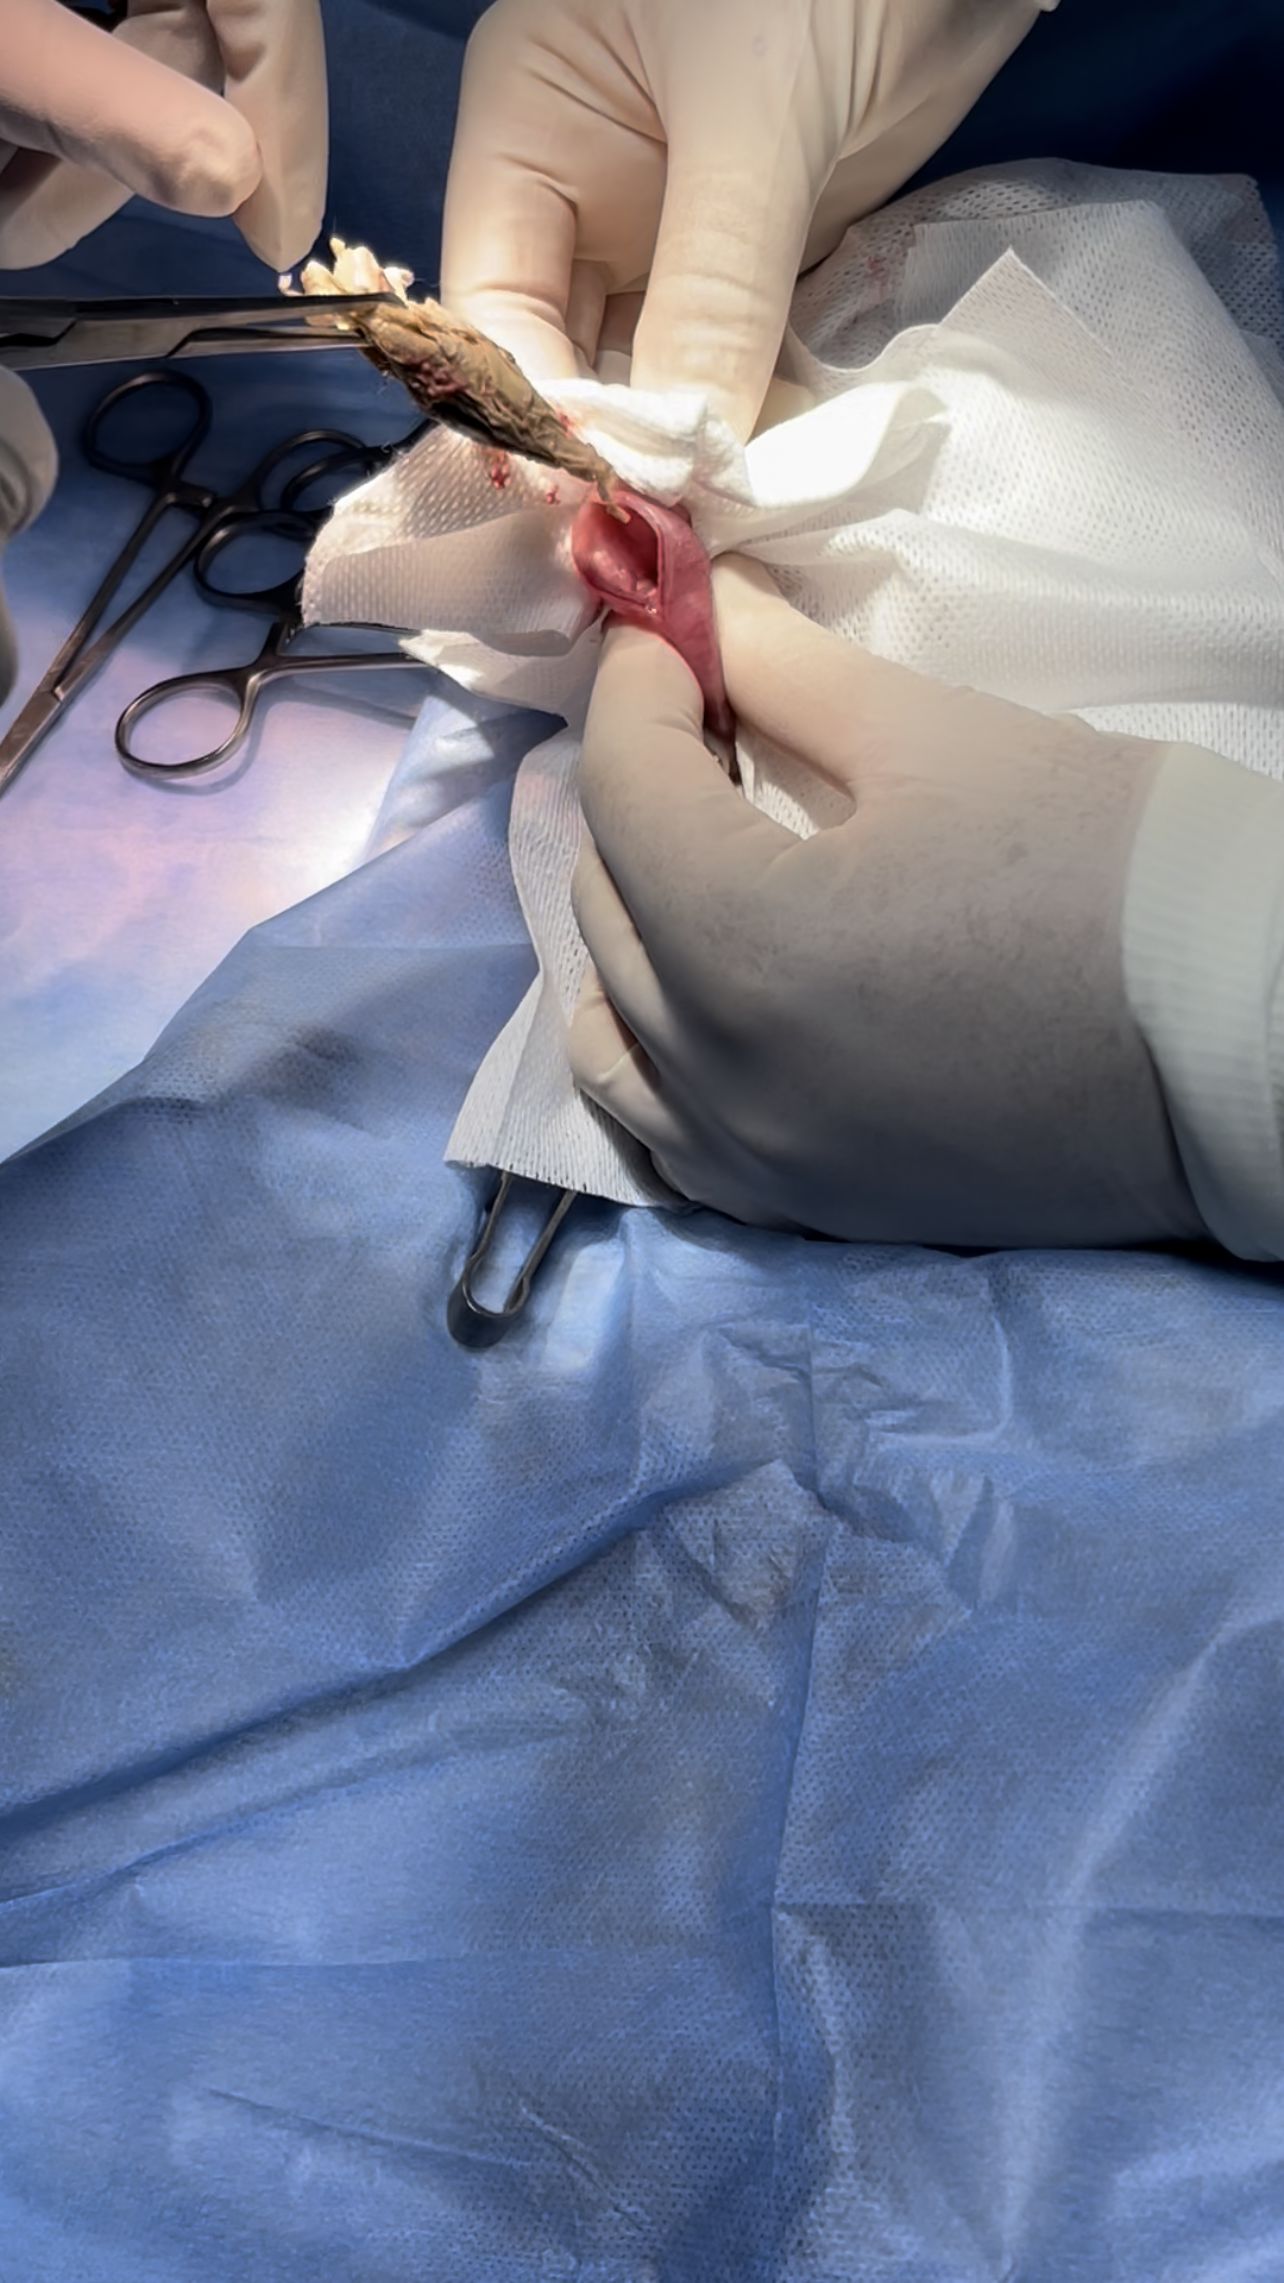

fb was consistent of a towel shreds

incision closed by double buried layers to prevent organ adhesion